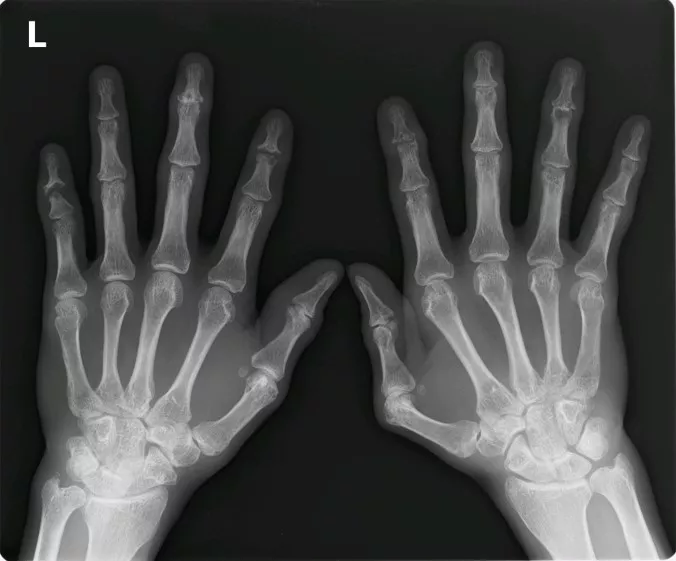

炎症性のDIP関節病変をみとめ、身体診察を再度行い確認すると手指に爪病変(写真3)、さらに足に指趾炎を認めた(写真4)。単純X線では、DIP関節周囲の骨新生像・靭帯骨棘形成および中節骨末端の骨びらん、特に左第5指DIP関節にはPencil-in-cup変形を認める(写真5)。以上から、最終診断としてRAにOAが合併した状態ではなく、当初から皮疹のない関節症状が先行したPsAであったと判断して、生物学的製剤を開始した。

写真5 両手X線写真